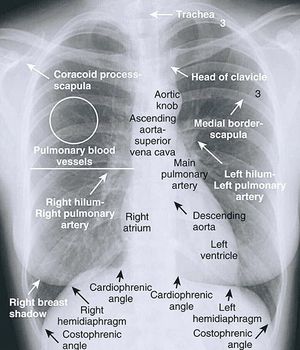

Radiografía simple de Tórax